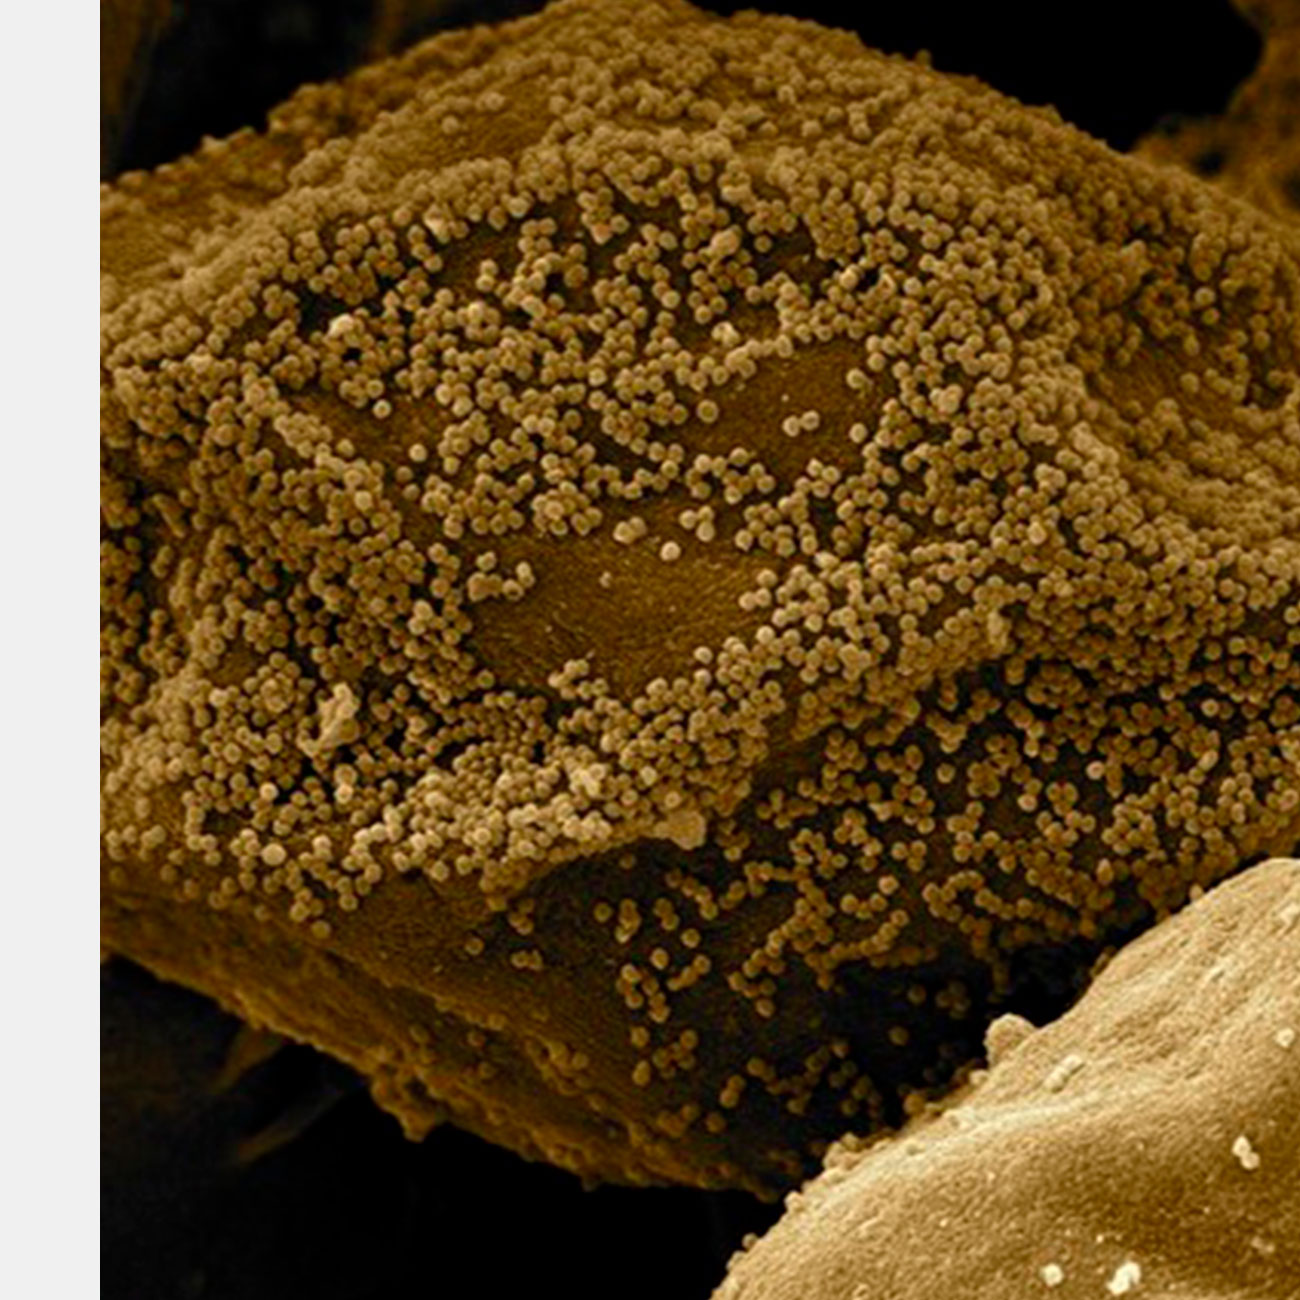

Американские ученые разработали вакцину от ВИЧ на основе мРНК. В доклинических испытаниях на макаках препарат снизил риск заразиться вирусом на 79 процентов. Вакцина все еще нуждается в доработке — она не генерирует оптимальные для защиты уровни антител, а кроме этого, ее надо вводить многократно. Исследование опубликовано в Nature Medicine.